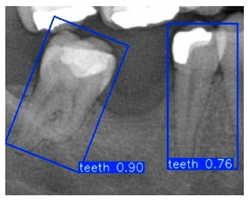

Although YOLOv10n-OBB demonstrated a slight advantage in overall classification accuracy, YOLOv8n-OBB achieved a relatively higher mAP50–95 of 78.75%. Furthermore, as illustrated in Figure 12, YOLOv8n-OBB generated predictions with higher confidence scores, and its detection boxes more comprehensively encompassed critical surrounding structures of the teeth, including both the crown and root regions. In contrast, YOLOv10n-OBB, despite exhibiting better classification accuracy, often produced detection boxes with insufficient coverage or positional deviations, which could compromise the accuracy and stability of subsequent localization and contour segmentation tasks. Considering both model performance and practical image application, the stable and reliable predictions provided by YOLOv8n-OBB better meet the requirements of fine-grained dental feature recognition. Moreover, its robustness is advantageous for downstream applications such as auxiliary line generation and implant pathway orientation.

Figure 12.

YOLO-OBB segmentation comparison.